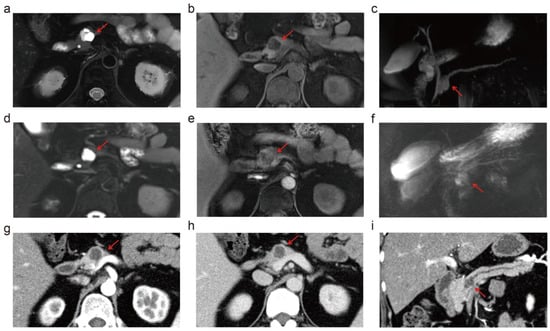

3.3. Depiction of PCL Imaging Features: 5.0 T vs. 3.0 T vs. MDCT